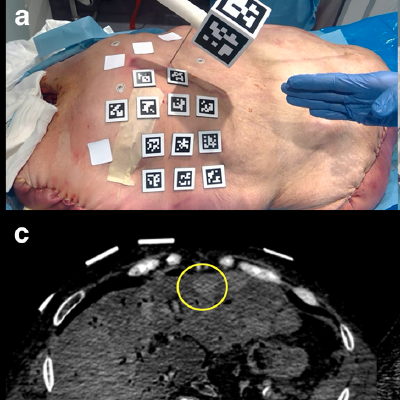

The Swiss researchers set out to assess the accuracy of AR-guided lumbar facet joint injections in a spine phantom. After a CT image was acquired from the phantom, a 3D model was reconstructed from the CT data and uploaded to the HoloLens. The model was then registered to the phantom, enabling a hologram to be created and used by the radiologist to guide the joint injections.

To test this method, two musculoskeletal radiologists performed both 20 AR-guided facet joint injections and 20 traditional CT-guided injections. After each needle was placed, a control CT study was performed. A third musculoskeletal radiologist then assessed the needle placement and categorized the result as either perfect (inside the joint space), acceptable (not necessary to re-place the needle), incorrect (need to re-place the needle), or unsafe (in the vicinity of nerves or vessels). The researchers also measured the procedure time from when the needle was first picked up by the radiologist until it was finally placed.